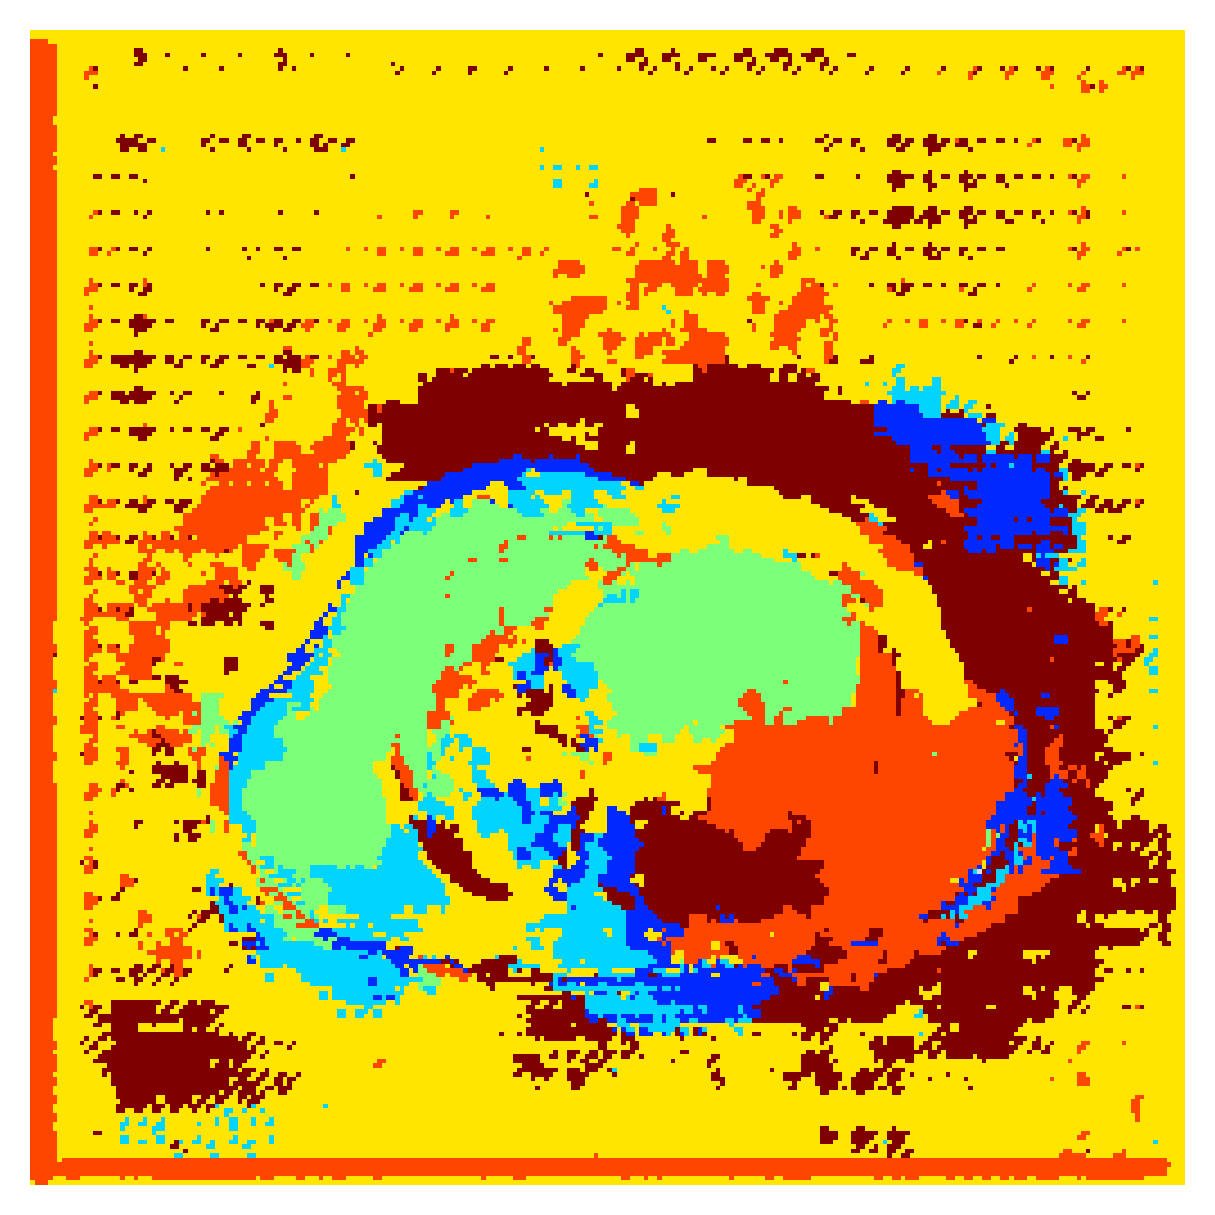

Qualitative comparison

|

|

|||

|

|

|

|

|

|

|

|

|

|

|

|

| (a) Ground truth | (b) , full | (c) , weak | (d) |

| (full) | supervision | supervision | |

|

|

|

|

|

|

|

|

|

|

|

|

| (e) | (f) | (g) | (h) CRF-loss |

In Figure 6 we provide qualitative results on a number of randomly chosen test set slices. Upon visual inspection, we can observe that training with the intensity-aware distances (particularly with and ) follows the image gradients better and is better at recovering the underlying shape than the Euclidean version. The CRF-loss seems to recover the shape of the myocardium and left ventricle to some extent, but fails entirely on the right ventricle.